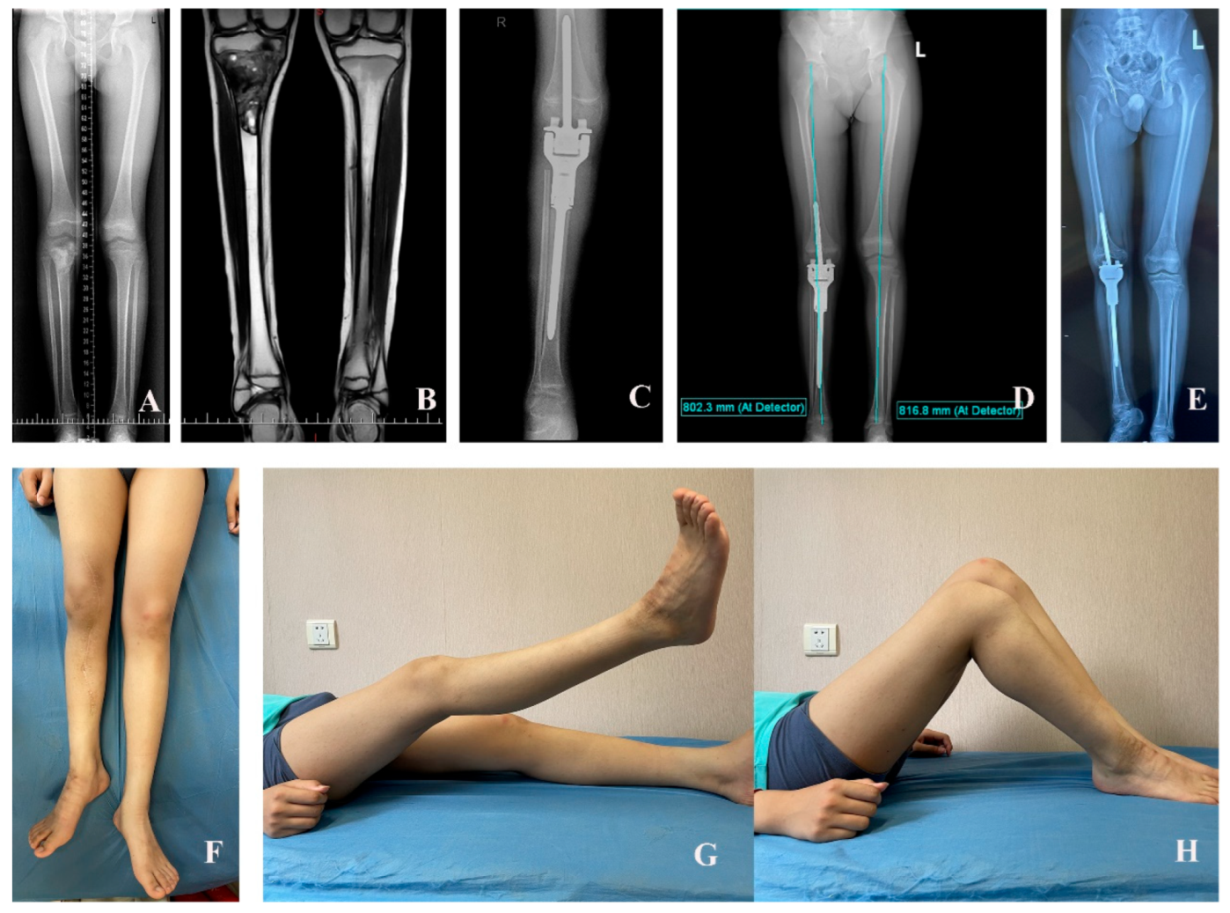

1. Introduction

3. Results

3.2. Functional Outcome

3.4. Femoral Discrepancy